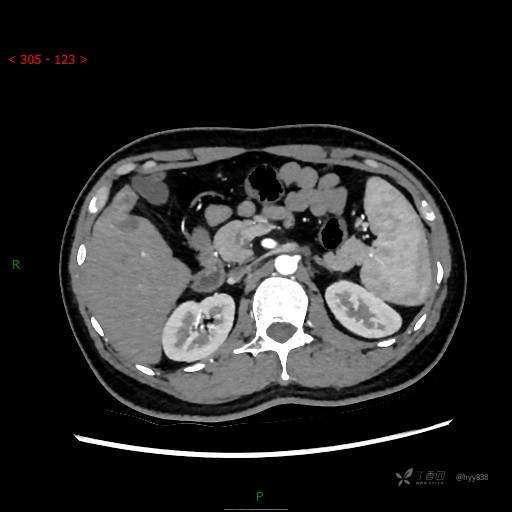

延迟期